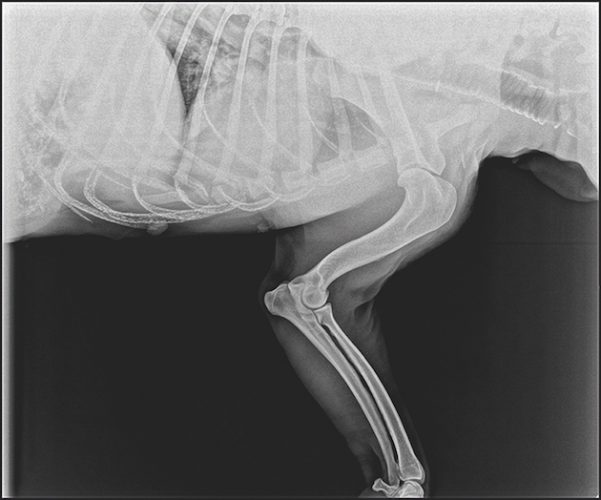

Health Checks For Labradors . The 13 common labrador health issues. We look at inherited labrador health problems, protecting your dog from infection, cancer and other diseases, epilepsy,dietary health issues and much more. When a dog is suffering from a luxating patella, their kneecap does not stay in the correct position. Discover why health screening is so important before breeding, to better the breed and give puppies the. Many labs suffer from joint problems such as hip or elbow dysplasia. What every owner should know. To assist breeders in fulfilling these requirements, akc has compiled the health testing requirements for each breed, organized by group on the left navigation of this page. It's important to understand the potential health issues that could affect your breed and the steps your breeder is taking to reduce your puppy's chances of inheriting health conditions.